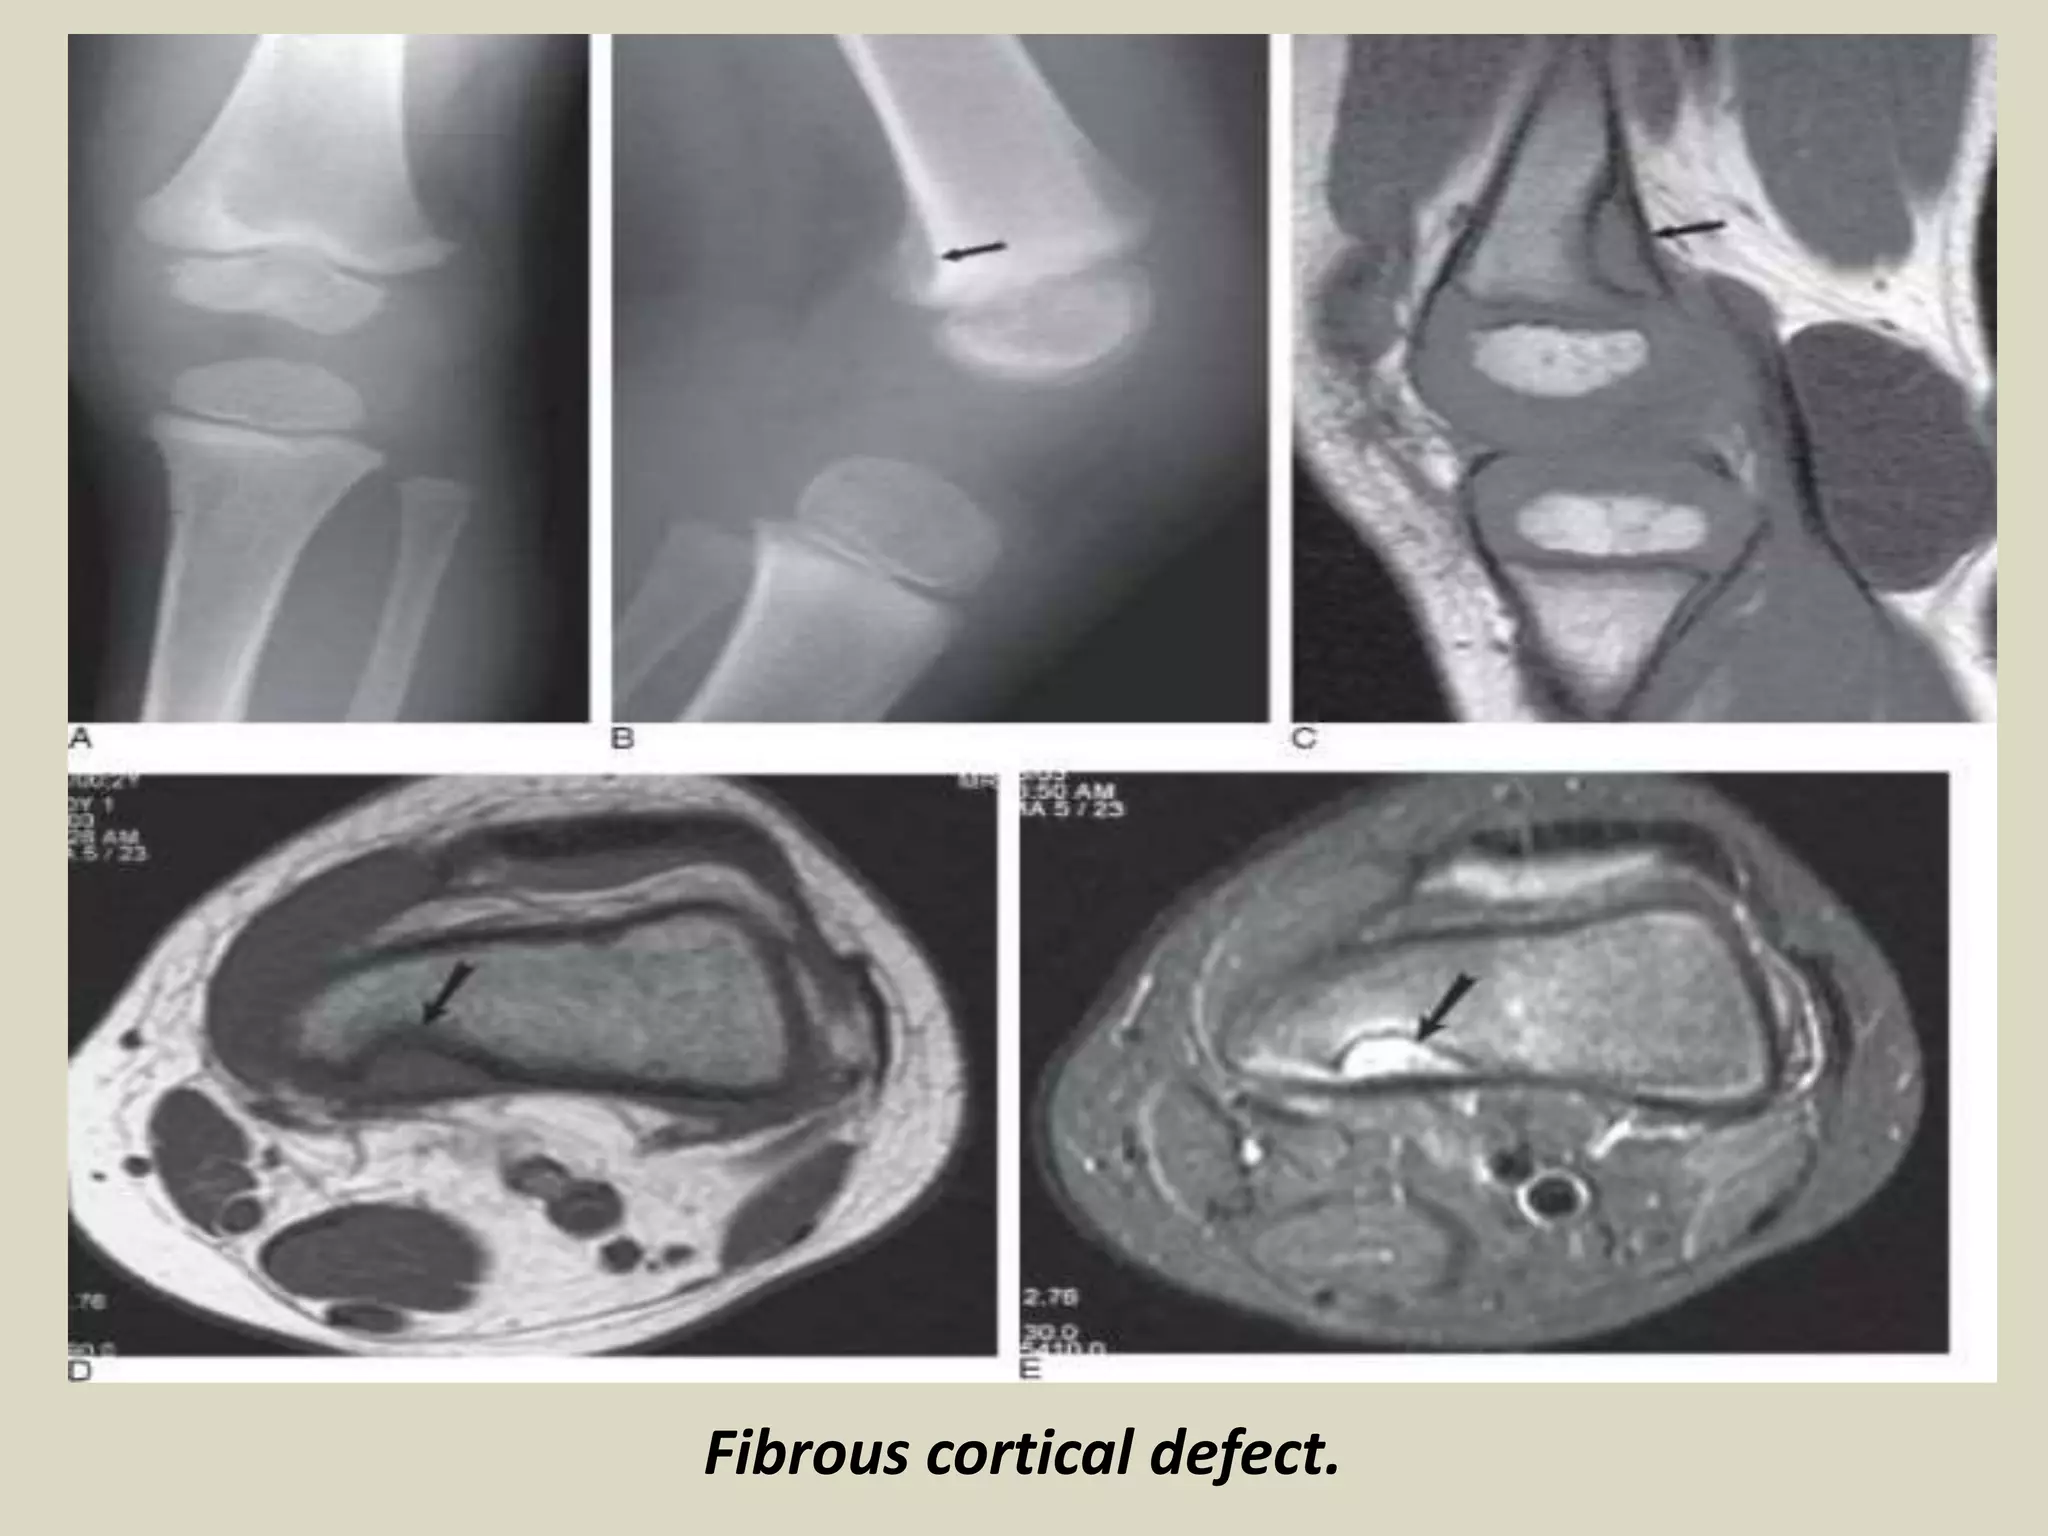

FIBROUS CORTICAL DEFECT/NON-OSSIFYING FIBROMA

Definition:

- Benign lesion of bone composed of spindle-shaped fibroblasts, arranged in a storiform

pattern, with a variable admixture of multinucleated osteoclast-like giant cells.

- Epidemiology:

- Patient have ranged in age from 6 to 74 years old. 30-40% in children.

- An average age of 4 years 54% of boys and 22% of girls, had a lesion involving the

cortex, and most regressed spontaneously over a period of approximately 2.5 years.

Site of involvement:

- Approximately 40% of NOF occur in the long bones, with distal femur, distal and proximal

tibia most frequently involved.

- As many as 25% of cases involve the pelvic bone, in particular the ilium.

Clinical findings:

- Majority of NOF cases are asymptomatic, and are an incidental discovery on X-rays

performed for other reasons.

- Larger lesion may cause pain that is probably secondary to microfractures or obvious

pathologic fracture.

- Most pathologic fractures develop through lesions that involve more than 50% of the

diameter of the bone.

-The vast majority of NOF are single, although they are multiple in 8% of cases.

- Multiple NOF may be associated with syndromes such as neurofibromatosis.

Imaging:

- Eccentric, lytic lesions centered within the metaphyseal cortex and adjacent medullary cavity

- of long tubular bones.

- Well demarcated with sclerotic margins and frequently harbor internal trabeculation.

FIBROUS TUMORS

Cortical fibrous defect

Fibrous cortical defect.